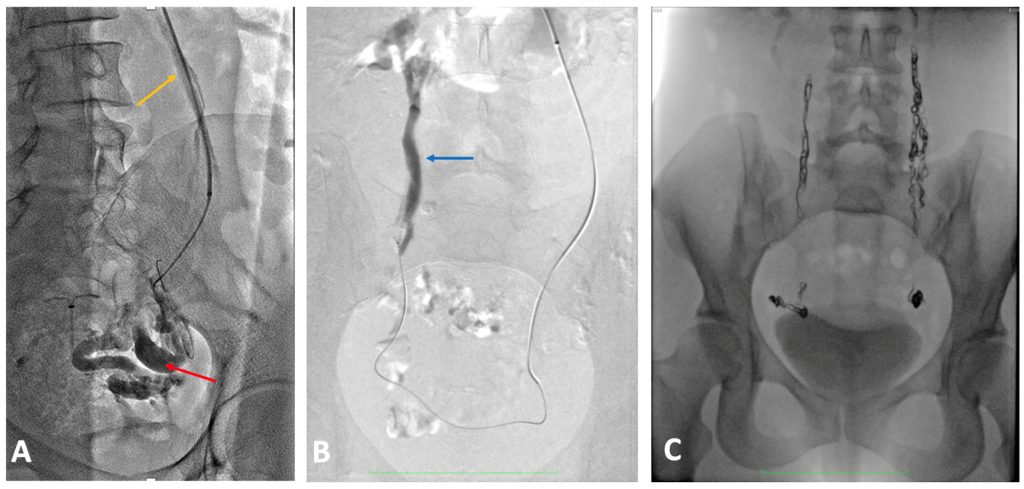

Рисунок 5. (А) Расширенные яичниковые вены: левая 9,1 мм (зеленая стрелка), а правая — 9,9 мм (желтая стрелка). (B) Варикозные вены в периматочном венозном сплетении (красные стрелки).

Рисунок 7. (А)-несостоятельная яичниковая вена, (В)- несостоятельная правая яичниковая вена, (С)-венография после эмболизации обеих яичниковых вен